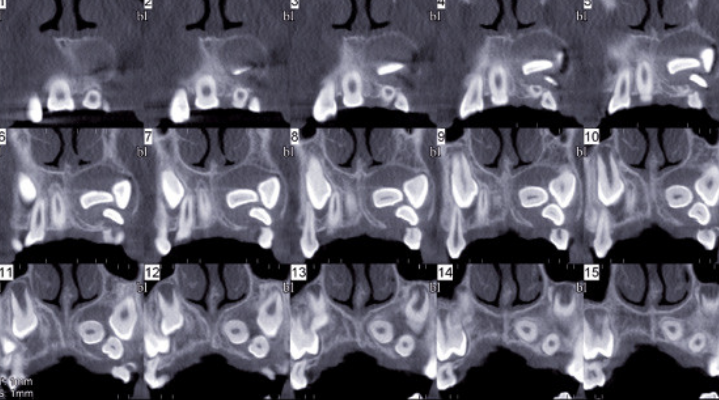

La Commission radioprotection dentaire et l’IRSN vous invitent à participer à une enquête sur l’utilisation du cone beam. Objectifs : établir des niveaux de référence diagnostique et mieux connaître les pratiques d’utilisation au niveau national.

Les niveaux de référence diagnostiques (NRD) sont des indicateurs de dose (valeurs chiffrées) permettant aux professionnels de l’imagerie de comparer leur pratique à une référence reflétant les pratiques nationales.

L’IRSN souhaite recueillir, « d’ici fin juin 2021 », les valeurs de doses délivrées aux patients pour différentes indications dentaires pour pouvoir en faire l’analyse.

Les indications incluses dans l’étude, sont :

Chez l’adulte

– Implant unitaire sans guide, sans sinuslift ;

– Implant multiple avec guide, sans sinuslift ;

– Implant maxillaire avec sinuslift ;

– Exodontie : dents de sagesse bilatérales ;

– Exodontie : dent incluse unitaire ;

– Evaluation du parodonte ;

– Endodontie.

Chez l’enfant

– Dent incluse (enfant d’environ 12 ans) ;

– Fente palatine (enfant d’environ 8-10 ans).

« Il est possible de participer pour tout ou partie seulement des indications listées, en fonction de vos équipements et de votre activité, indique l’IRSN. Pour que les résultats de l’étude soient représentatifs des pratiques en France, il est nécessaire que le panel de participants soit aussi large que possible ».